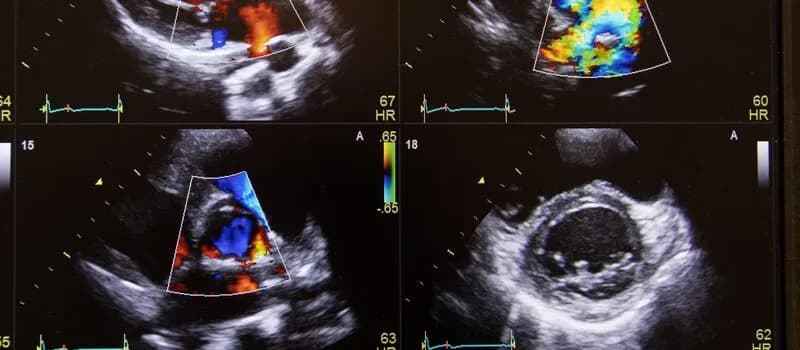

Tag jak ocenić wyniki badania dopplera